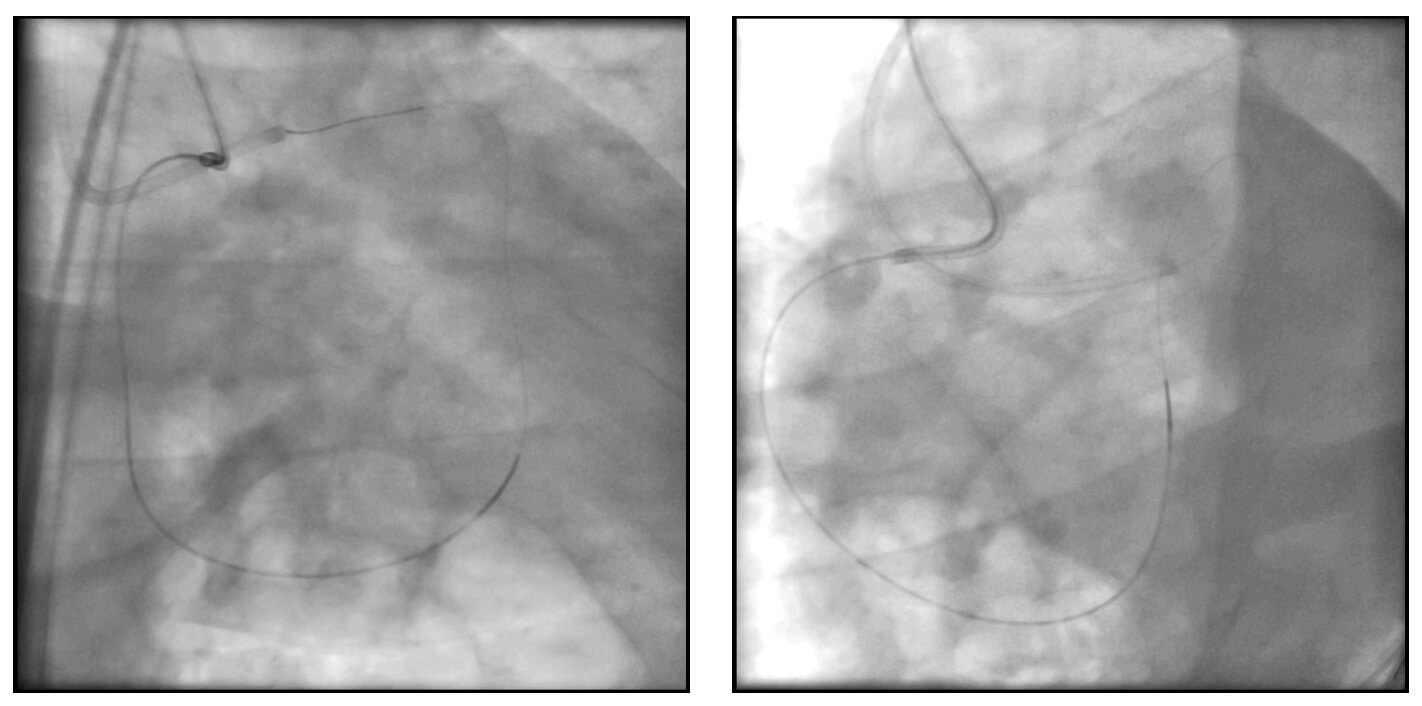

Se realizó inyección de contraste dual en ambas arterias coronarias (arteria coronaria derecha con catéter Amplatz Right y arteria descendente anterior izquierda con catéter EBU). Clasificación de Werner: 2 puntos.

Se avanzó una guía intracoronaria Asahi Sion Black desde la arteria coronaria derecha, siguiendo el trayecto de una de las ramas septales, logrando acceso al tercio medio de la arteria descendente anterior izquierda, con soporte de microcatéter Turnpike. Posteriormente, la guía fue reemplazada por una de 300 cm para su externalización a través del catéter ubicado en el tronco de la coronaria izquierda.